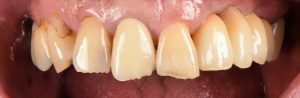

大きな虫歯と根の破折で抜歯適応となった歯を複数本インプラントで再建した症例

初診時。複数本のブリッジがグラついて食べ物が噛めないとのことでご来院されました。レントゲン写真で精査すると、土台に大きな虫歯ができて、一部脱離していることがわかりました。ブリッジを外してみると、そこに…